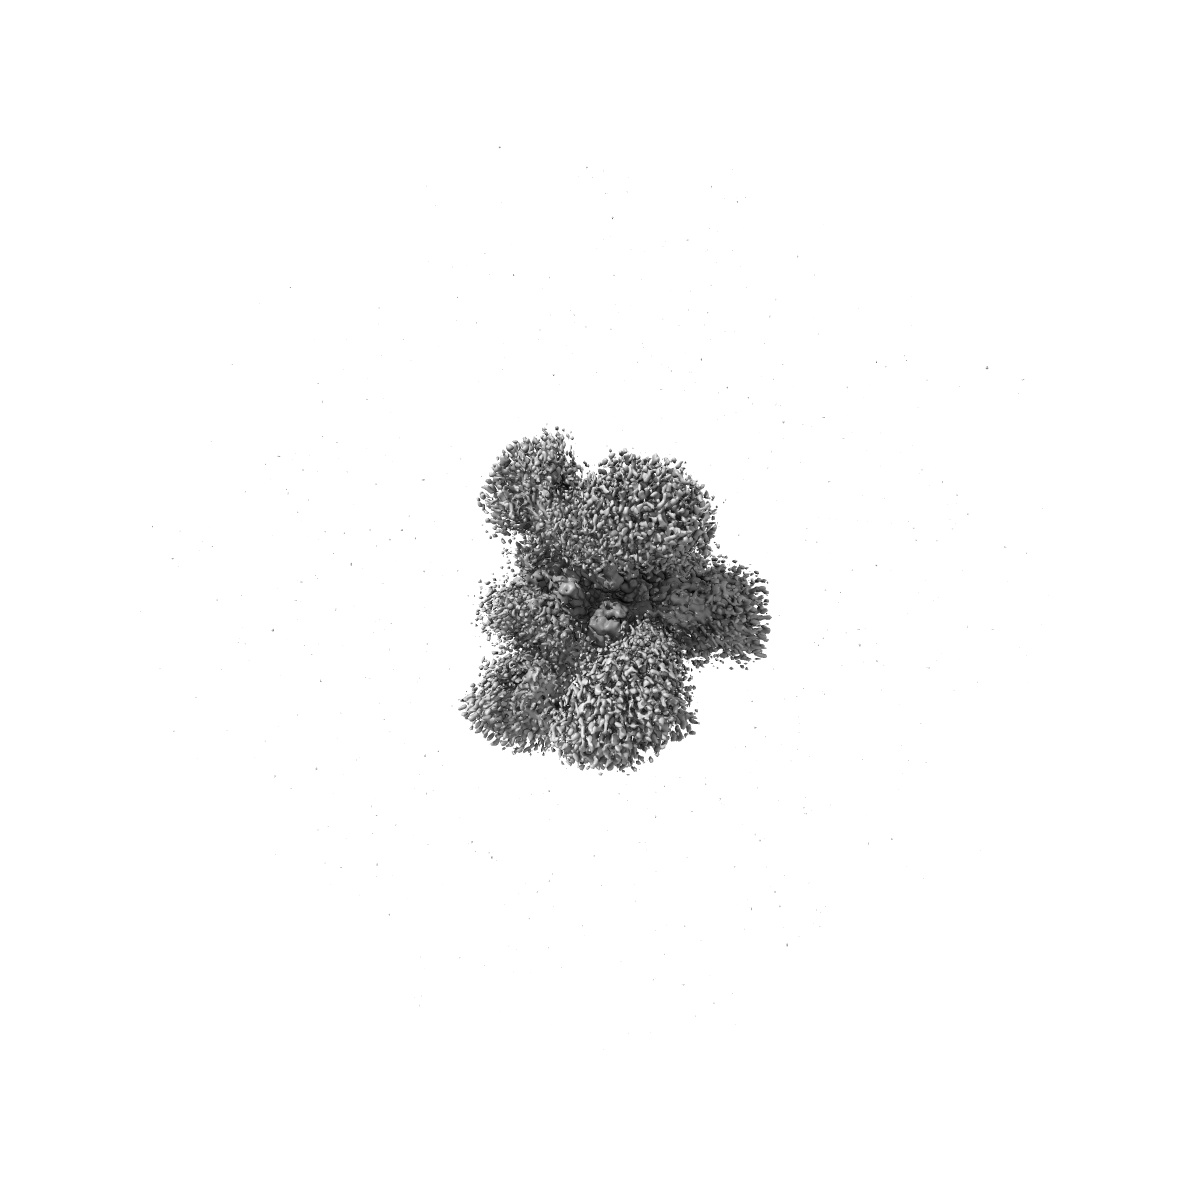

Cryo-EM structure of mink variant Y453F trimeric spike protein bound to two mink ACE2 receptors

Single-particle3.36 Å

Sample: Cryo-EM structure of mink variant Y453F trimeric spike protein bound to two mink ACE2 receptors